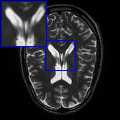

Limited by imaging systems, the reconstruction of Magnetic Resonance Imaging (MRI) images from partial measurement is essential to medical imaging research. Benefiting from the diverse and complementary information of multi-contrast MR images in different imaging modalities, multi-contrast Super-Resolution (SR) reconstruction is promising to yield SR images with higher quality. In the medical scenario, to fully visualize the lesion, radiologists are accustomed to zooming the MR images at arbitrary scales rather than using a fixed scale, as used by most MRI SR methods. In addition, existing multi-contrast MRI SR methods often require a fixed resolution for the reference image, which makes acquiring reference images difficult and imposes limitations on arbitrary scale SR tasks. To address these issues, we proposed an implicit neural representations based dual-arbitrary multi-contrast MRI super-resolution method, called Dual-ArbNet. First, we decouple the resolution of the target and reference images by a feature encoder, enabling the network to input target and reference images at arbitrary scales. Then, an implicit fusion decoder fuses the multi-contrast features and uses an Implicit Decoding Function~(IDF) to obtain the final MRI SR results. Furthermore, we introduce a curriculum learning strategy to train our network, which improves the generalization and performance of our Dual-ArbNet. Extensive experiments in two public MRI datasets demonstrate that our method outperforms state-of-the-art approaches under different scale factors and has great potential in clinical practice.